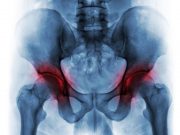

Intra-Articular Injection of Triamcinolone Beneficial in Hip Osteoarthritis

Pain improved with ultrasound-guided intra-articular hip injection of corticosteroid and local anesthetic added to best current treatment